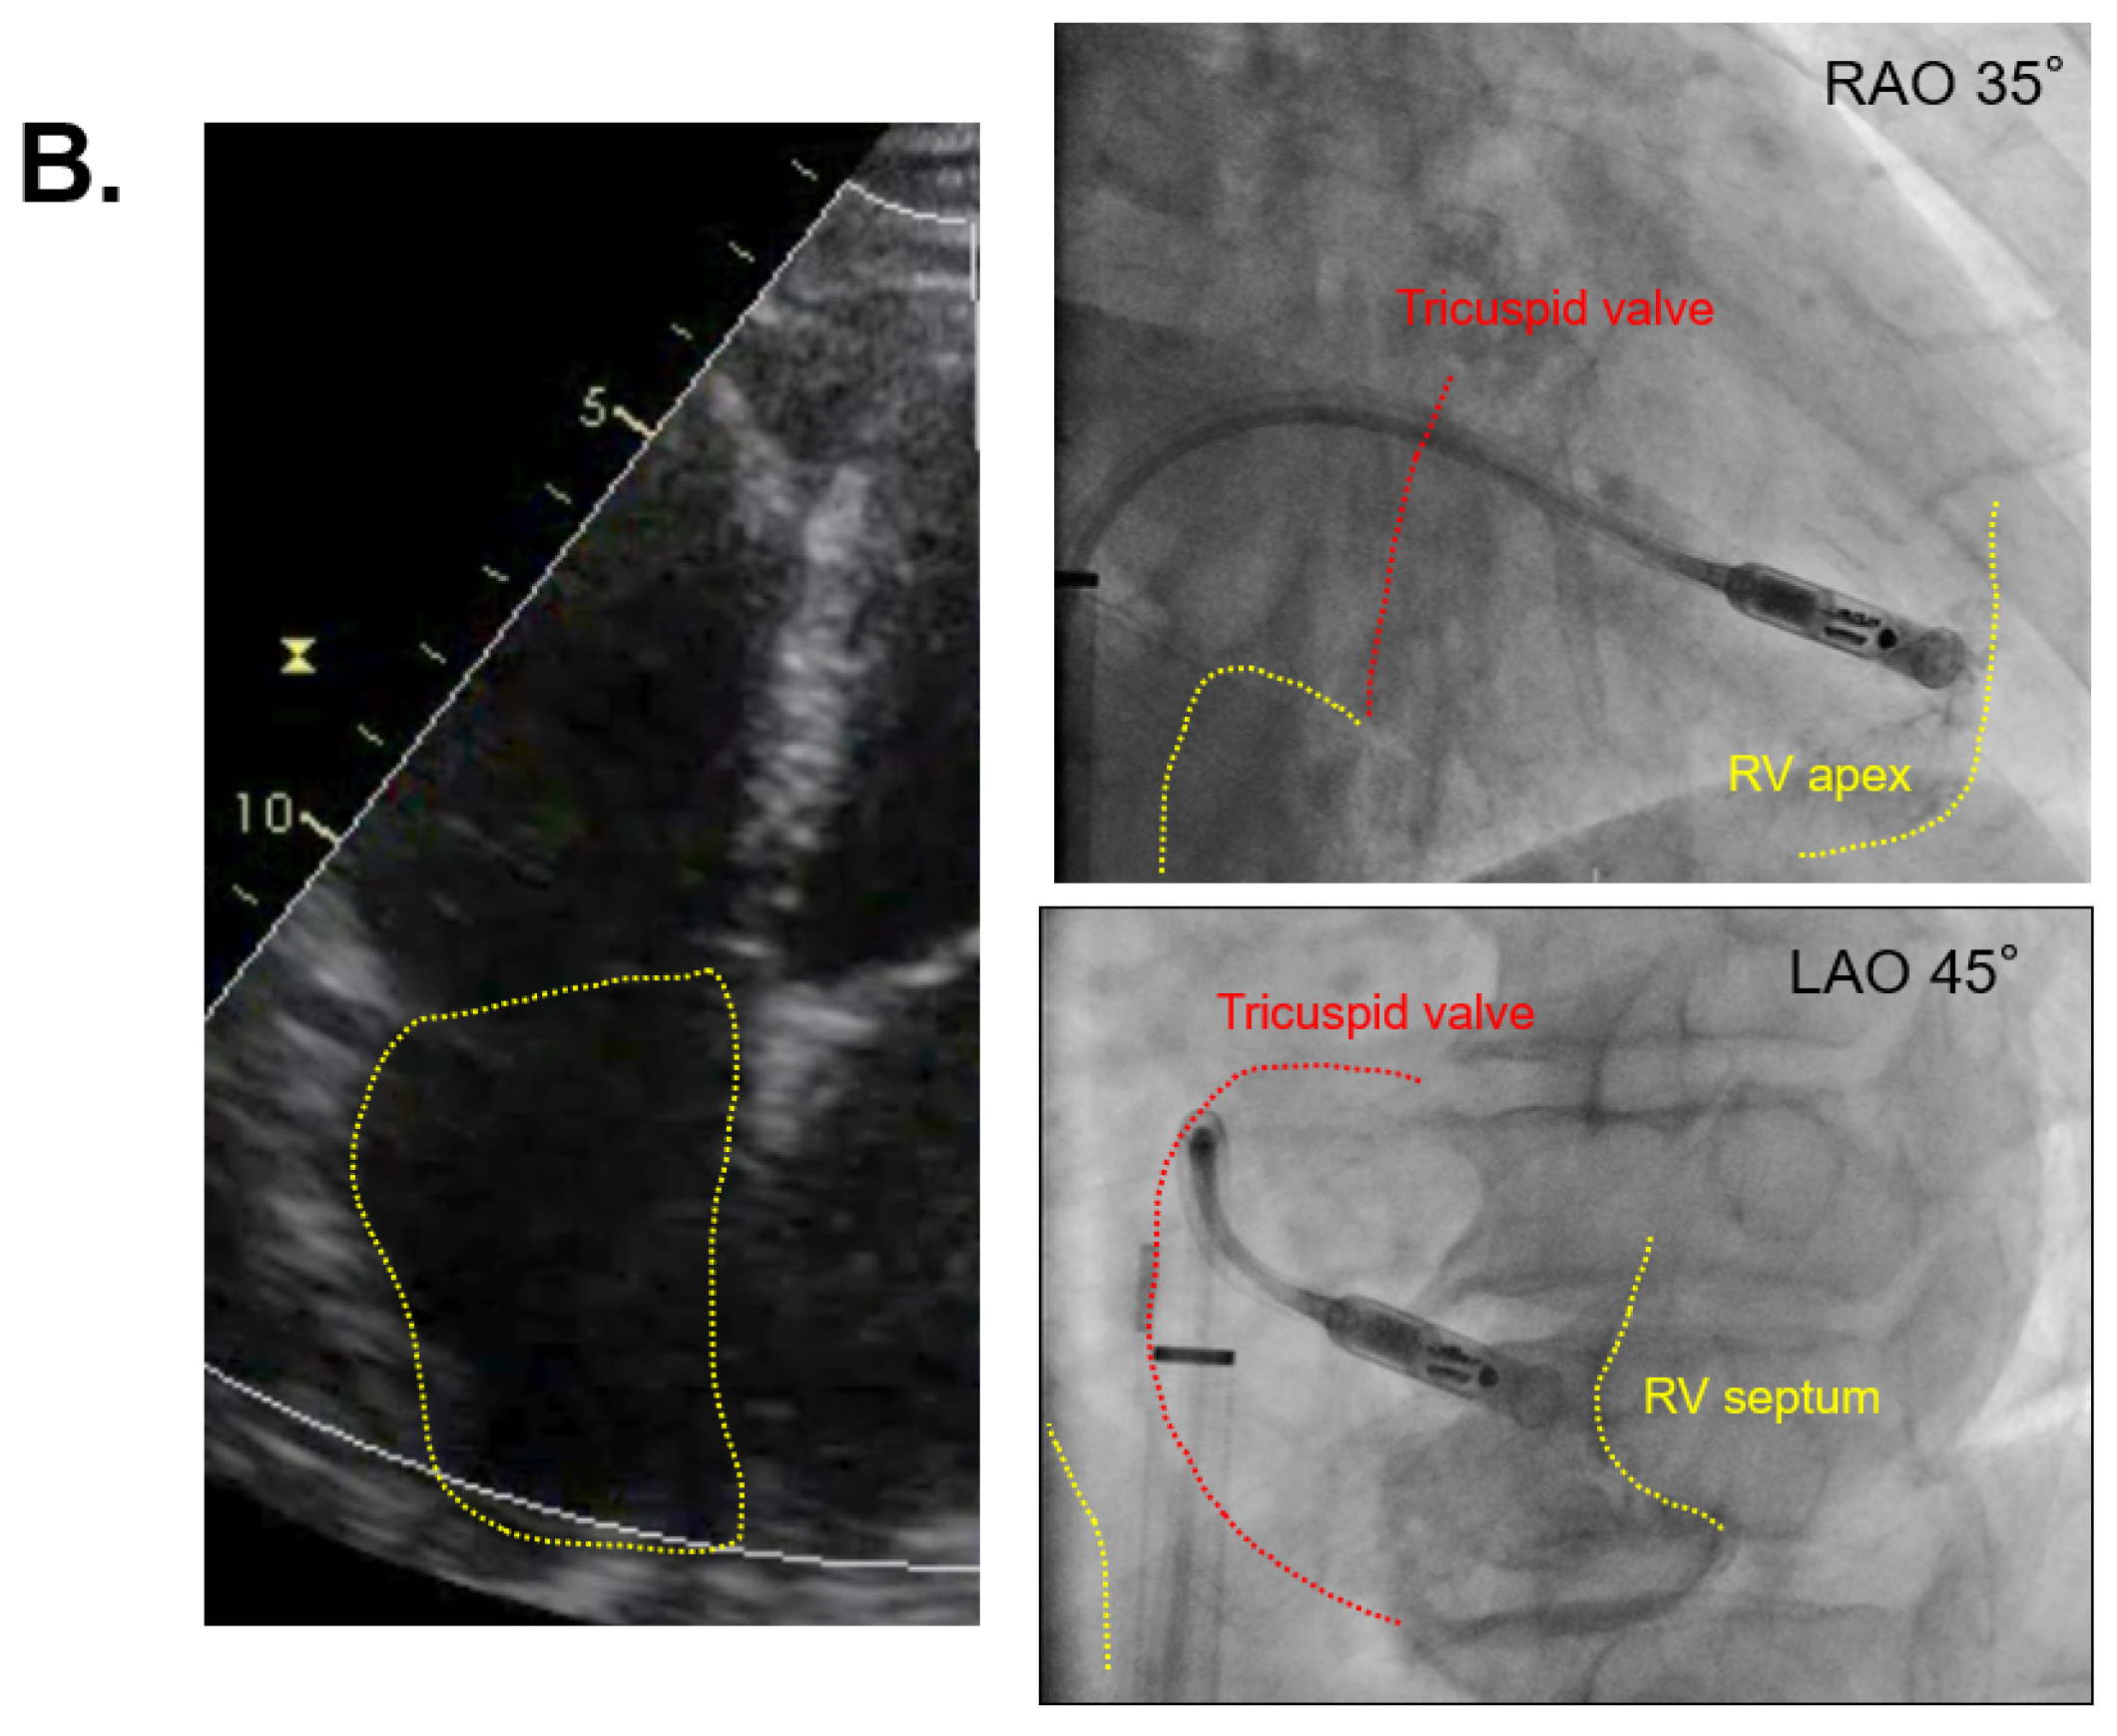

The two cases with the shortest and longest procedure times are displayed in Figure 3A,B, respectively. The patient of Figure 3A had a smaller right atrium with 3.3 cm right atrial diameter and 14.7 cm2 right atrial area, and a procedure time of 30 min. The patient of Figure 3B had a larger right atrium with 4.3 cm right atrial diameter and 24.7 cm2 right atrial area, and the procedure time was 185 min (Figure 3B).

Figure 3.

Echocardiography in the shortest and longest procedures. (A) The case of smaller right atrium with 30 min of procedure time; (B) the case of larger right atrium with 185 min of procedure time; echocardiographic views indicate four chambers, viewing from the apex, and yellow dashed lines indicate the right atrium; IVC = inferior vena cava, RV = right ventricle.